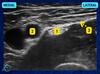

Sobre o bloqueio nervoso na fossa poplítea, assinale a opção que correlaciona corretamente a indicação numérica da figura acima e a estrutura anatômica apontada.

146